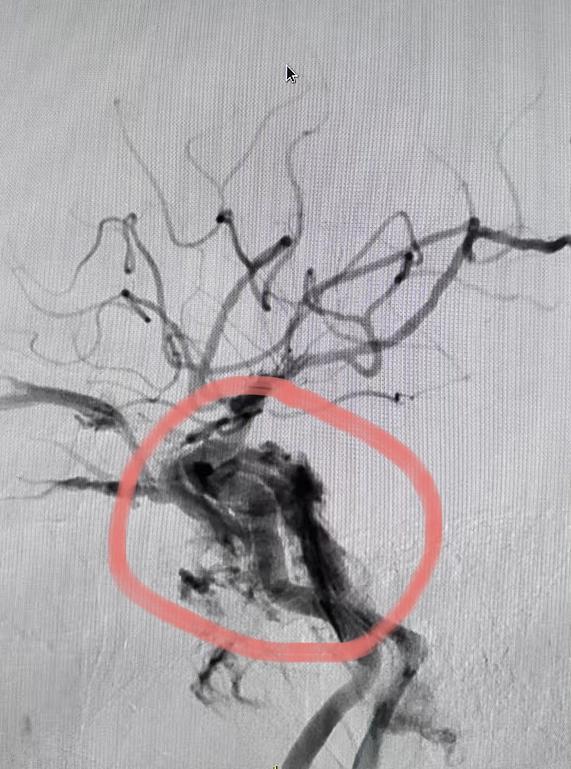

▲术前造影显示:颈内动脉血流入海绵窦瘘

入院后进一步完善相关检查,邀请多学科会诊评估后,医疗团队为周先生制定了手术方案,并于2月18日由,康超文副主任医师团队为其施行颈内动脉海绵窦瘘弹簧圈栓塞术。手术历时3小时,成功将弹簧圈置入瘘口,有效阻断异常血流,恢复正常的血液循环。